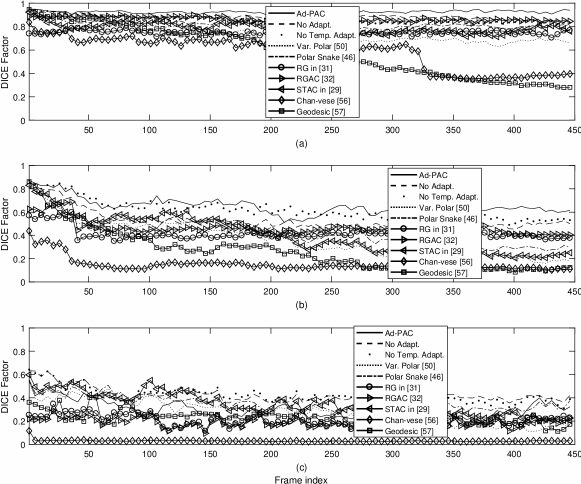

V-G Influence of IJV Variation

The CSA of the IJV undergoes a wide range of variation that typically present a challenge for AC models as they are relatively sensitive to this parameter. This often results in a failure to track and converge to the edges of the object. To study the influence of variation, the ultrasound videos were categorized into three groups i) less than 10 percent, ii) between 10 and 90 percent and iii) more than 90 percent variations. Note that, in the case of more than 90 percent variation, the IJV shape deforms from oval or 1+ apical shape to fully collapsed, resulting in this category resembling the one in Fig. 16-(c). The numerical results based on this categorization are shown in Fig. 17. As one can see from Fig. 16-(a), when the CSA of the IJV undergoes small variations, the average DICE factor is always greater than 0.94. In Fig. 16-(b) with the variation between 10 to 90 percent, the Ad-PAC algorithm still performs well with an average DICE factor of 0.64 and still outperforms the other algorithms. Finally from Fig. 16-(c), it is observed that when the IJV undergoes large variations, all algorithms gradually lose tracking. Ad-PAC algorithm does not always outperform Ad-PAC without adaptation in these scenarios.